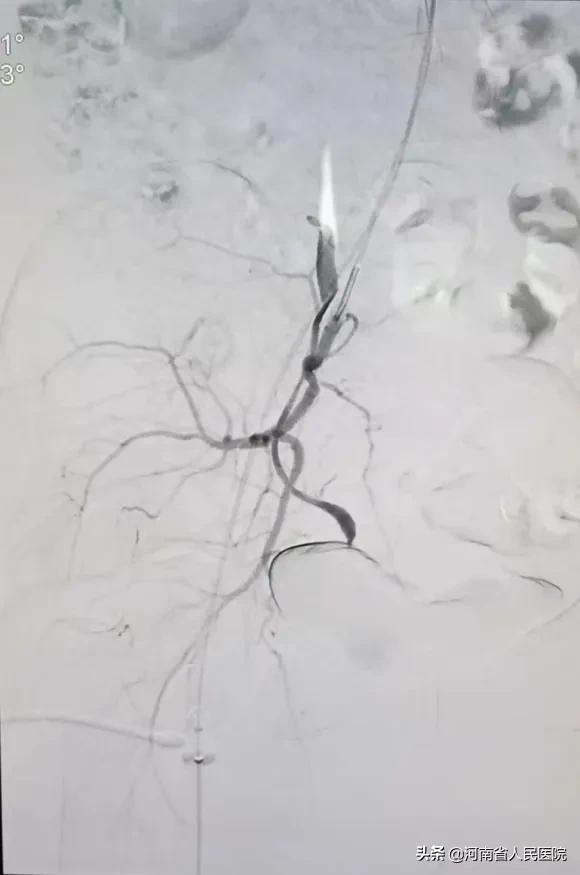

谁知一做血管造影才发现:患者两侧子宫动脉均不同于一般人,一侧是由 卵巢动脉 (锯齿状血管)“长途奔袭”去供应子宫血液,一侧是从 阴部内动脉 发出。

两个血管发出角度都很 刁钻 ,血管走形迂曲又比较细。

做这样的血管介入类似于医学版 “爬雪山过草地” ,大家不禁倒吸一口冷气!

综合介入科主治医师刘建文带领刘玉岩医师,小心翼翼,利用导管、导丝巧妙配合,经过两个多小时的艰苦奋战,浑身衣服都湿透了,最终 成功将两侧血管栓塞 !

栓塞后子宫的供血动脉不再显影